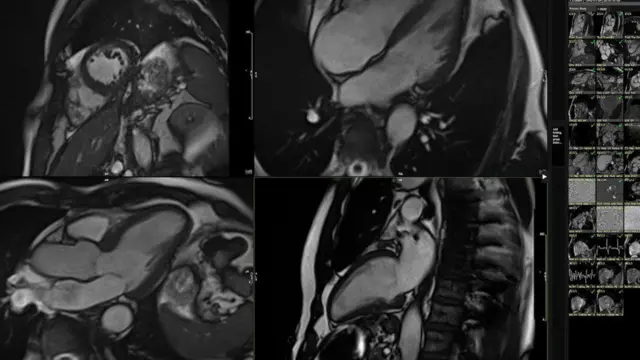

El proceso implicó realizarme una resonancia magnética (MRI) de mi corazón después de algo de ejercicio ligero.

El sistema analizó cientos de pequeños detalles en el movimiento 3D de mi resonancia magnética y los comparó con los de 5.000 personas de distintas edades que habían llevado estilos de vida saludables.